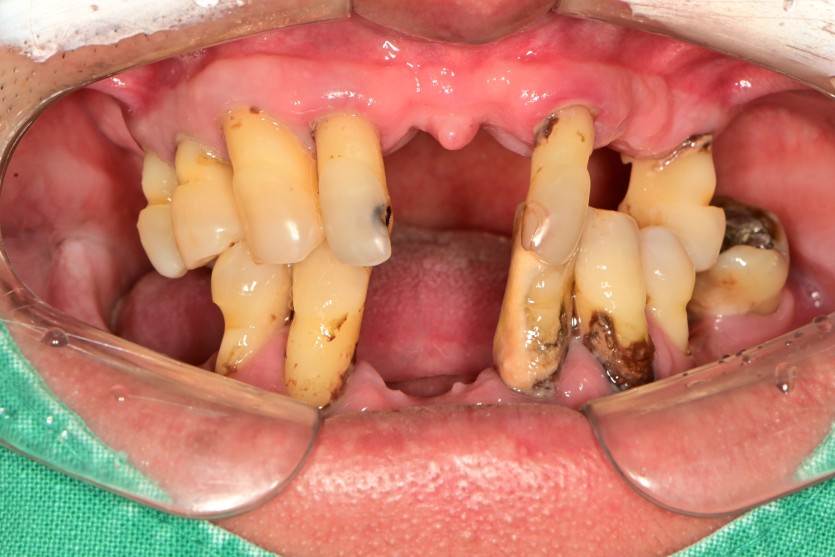

만 50세 전체임플란트 증례입니다.

전체 임플란트 증례입니다.

18개의 임플란트로 완성하였습니다.